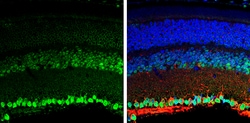

| Immunohistochemistry (Frozen), Immunohistochemistry (Paraffin), Western Blot, Immunocytochemistry | |